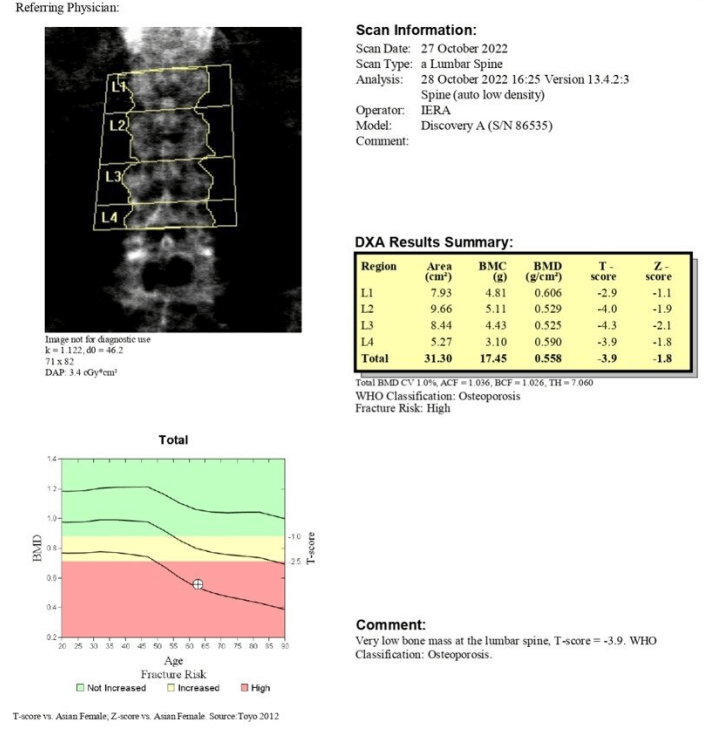

Spine Upon Admission

- 1st DXA scan done upon admission

2nd DXA scan done after 12 months of Romosozumab therapy

- Spine BMD changes: [(0.739-0.558)/0.558] X 100% = 32.4%